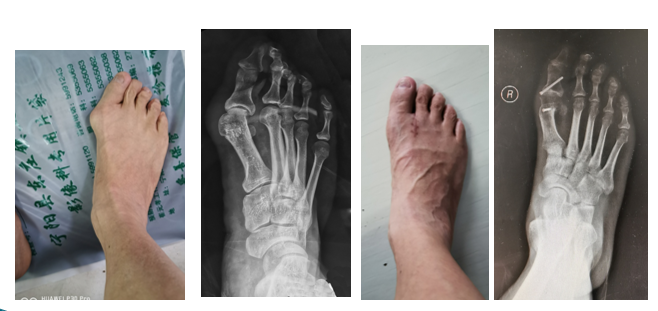

专业特长:足踝畸形、退变如:拇外翻、平足、高弓足、马蹄足、类风湿足、糖尿病足、踝关节畸形、趾甲畸形,足踝部骨折、脱位与韧带损伤,脊柱侧弯和后凸畸形的生物力学和矫形,创伤后遗症如骨髓炎、骨不连、畸形愈合等,积累了丰富的临床经验。

在东庄卫生院行拇外翻矫形术